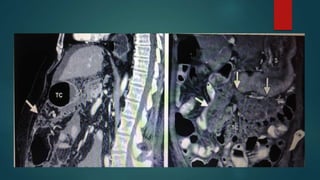

Inframesocolic spaces

below the transverse mesocolon and

transverse colon as far as the true pelvis.

 divided in two unequal spaces

RIC/LIC by the root of the mesentery

of the small intestine.

 It contains the right and left paracolic

gutters lateral to the ascending and

descending colon.